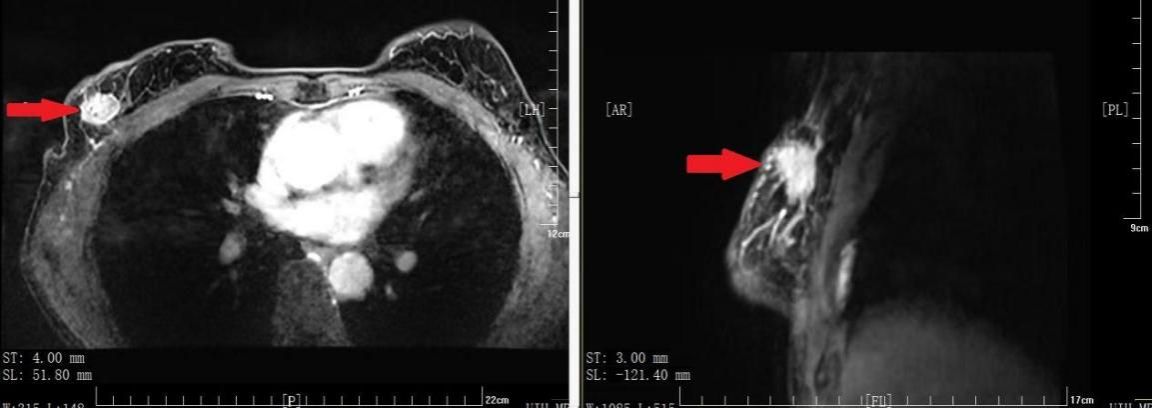

图2 常规大小乳房仰卧位MRI图像红色箭头指示肿瘤